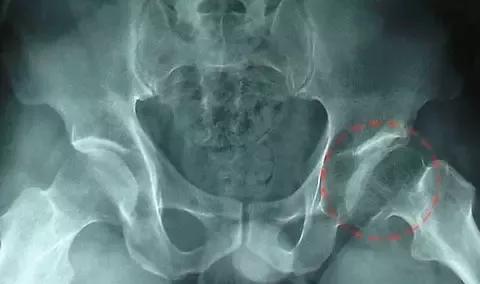

左侧股骨头坏死影像资料

股骨头坏死防治专题之:股骨头坏死影像学病理分型

股骨头坏死塌陷的影像,临床及病理学 [精华]